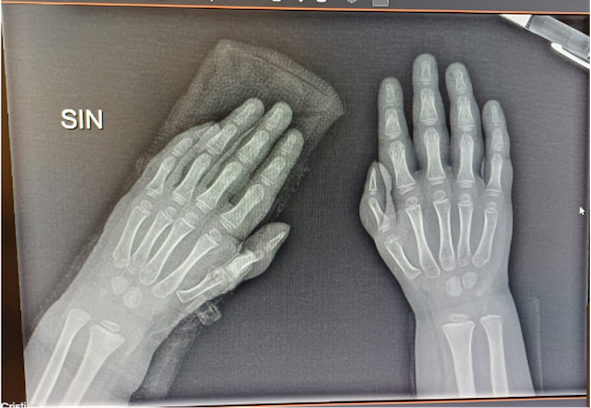

L’esame obiettivo del paziente mette in evidenza lieve dismorfismo del I dito di entrambe le mani, confermato anche radiograficamente (Figura). L’associazione di citopenia trilineare, anomalie scheletriche e macrocitosi pongono il sospetto di anemia di Fanconi (FA). La positività del DEB test conferma la diagnosi. Le indagini genetiche rilevano mutazione in omozigosi del gene FANCA. Il bambino viene affidato all’unità di Oncoematologia pediatrica per la prosecuzione delle cure e si avviano le procedure per la ricerca di un donatore compatibile di midollo osseo; il piccolo è in attesa di trapianto.